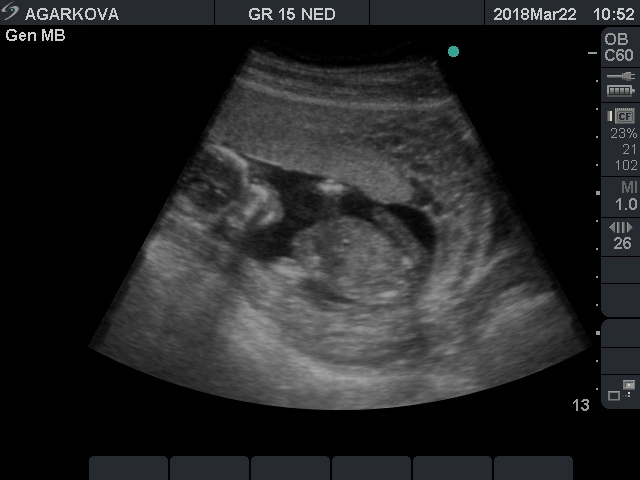

Мальчик или не мальчик?...

Нет, ну на последнем фото определенно мальчик!!И мошонка и писюн хорошо видны.У меня похожие фотки причандалов от двух сыновей))

Девочки, всем спасибо!:) Раз и тут единогласно мальчик, значит сомнений нет. Всегда любила голубой цвет. 😘